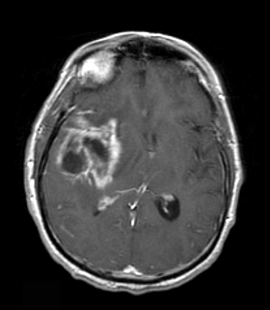

The patient is a 58-year-old woman who was diagnosed at an outside hospital with a World Health Organization (WHO) grade III non–contrast-enhancing right frontal anaplastic astrocytoma, with spread into the genu of the corpus callosum.